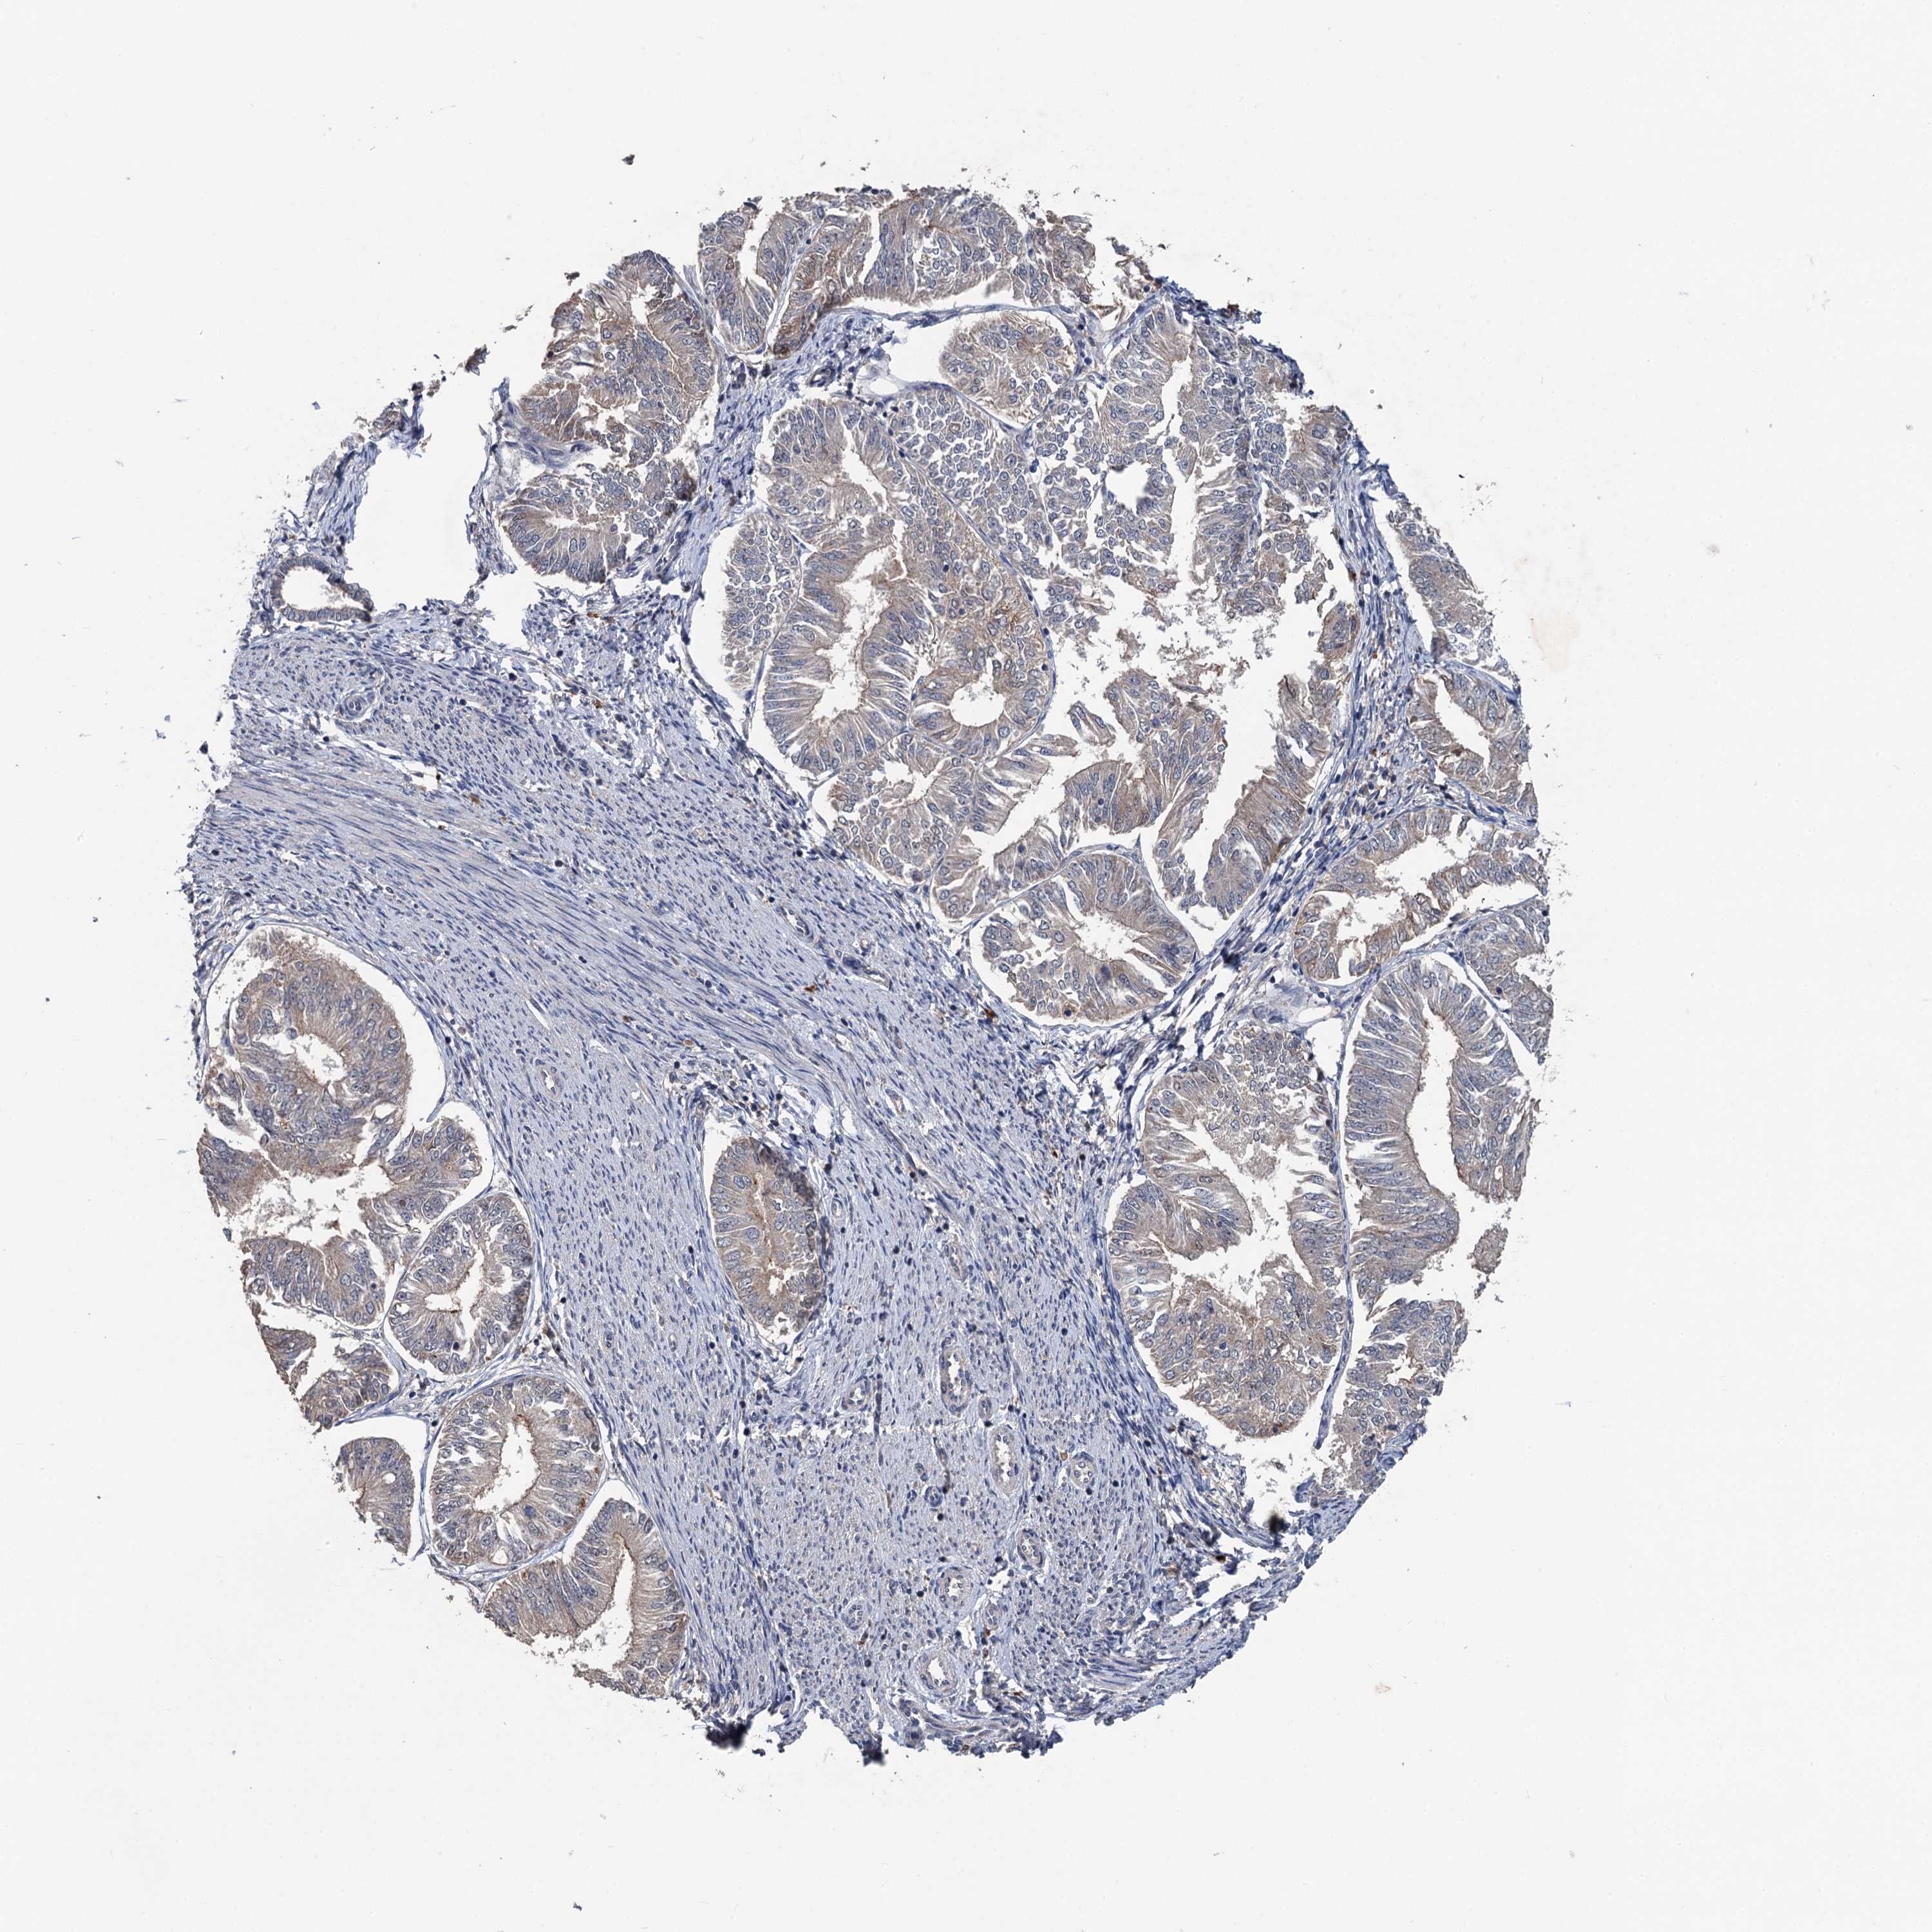

ENDOMETRIAL CANCER - Protein expressioni

A mouse-over function shows sample information and annotation data. Click on an image to view it in a full screen mode. Samples can be filtered based on level of antibody staining by selecting one or several of the following categories: high, medium, low and not detected. The assay and annotation is described here.

Note that samples used for immunohistochemistry by the Human Protein Atlas do not correspond to samples in the TCGA dataset.

Antibody stainingi

Antibody staining in the annotated cell types in the current human tissue is reported as not detected, low, medium, or high, based on conventional immunohistochemistry profiling in selected tissues. This score is based on the combination of the staining intensity and fraction of stained cells.

Each image is clickable and will lead to virtual microscopy that enables deeper exploration of all samples and also displays staining intensity scores, fraction scores and subcellular localization as well as patient and tissue information for each sample.

Antibody HPA039843

Staining

High

Medium

Low

Not detected

Intensity

Strong

Moderate

Weak

Negative

Quantity

>75%

75%-25%

<25%

None

Location

Nuclear

Cytoplasmic/membranous

Cytoplasmic/membranous,nuclear

Adenocarcinoma, NOS